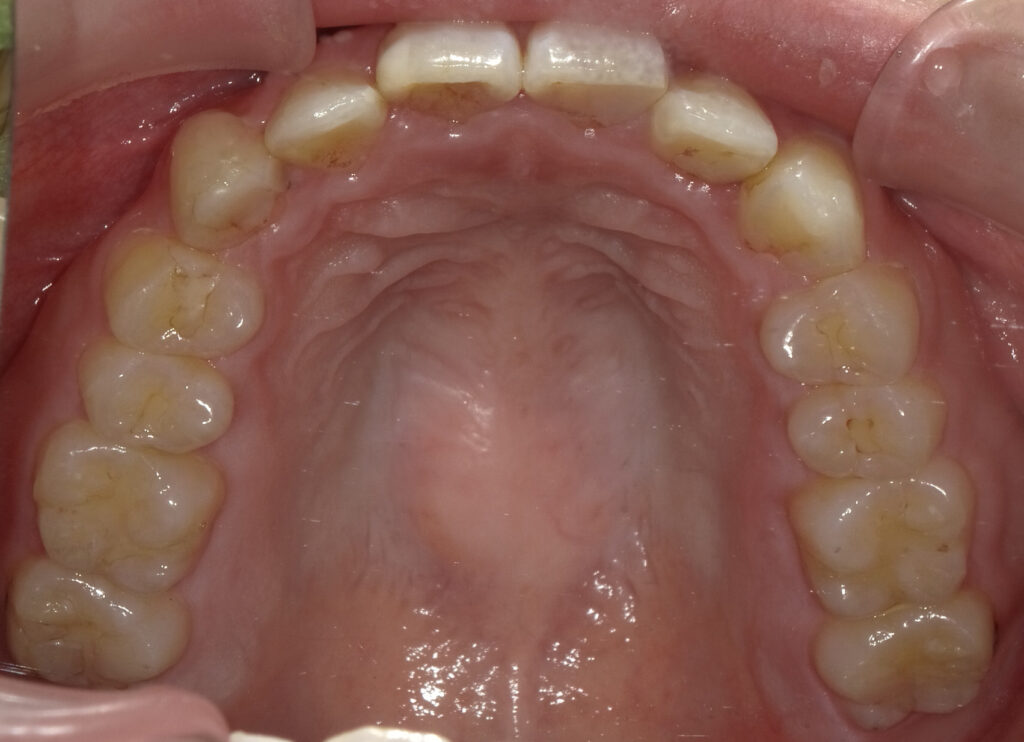

上顎

治療後